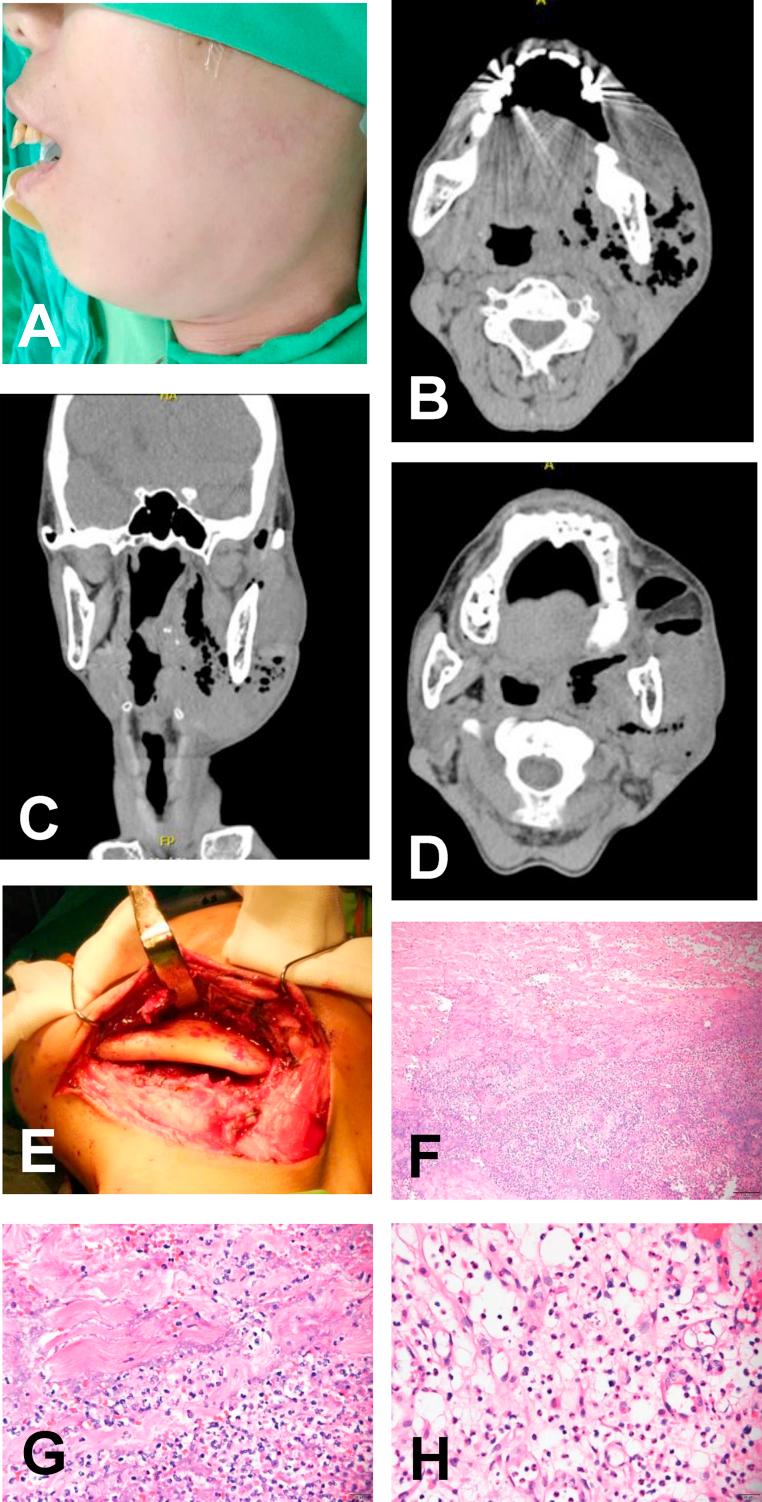

Necrotizing myositis - Case report.

https://cdn.ncbi.nlm.nih.gov/pmc/blobs/5032/7816035/b1bdf9faa44f/gr1.jpg